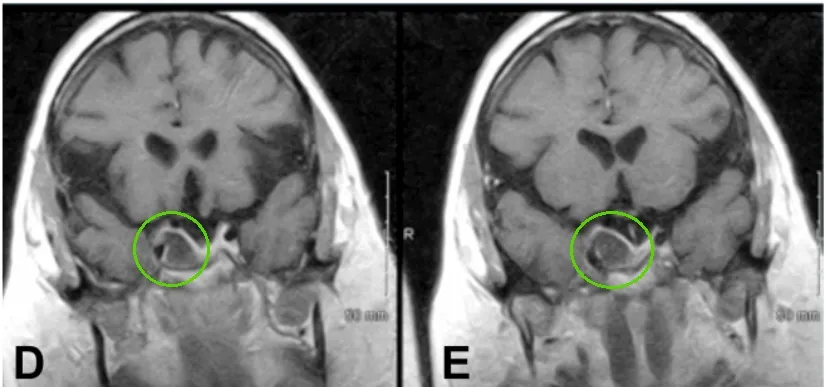

41歲的艾拉罹患巨大無功能性垂體腺瘤,曾在其他醫(yī)院進行顯微鏡下經(jīng)蝶竇入路切除腫瘤。由于右側(cè)海綿竇內(nèi)小殘余腫瘤的又長大了,她便接受了放療。

進行放療一年后,她的右眼眼皮無法控制地耷拉下來,看東西出現(xiàn)重影,眼球轉(zhuǎn)動困難——這是典型的動眼神經(jīng)麻,MRI檢查發(fā)現(xiàn)她的右側(cè)海綿竇內(nèi)腫瘤復(fù)發(fā)了,而且正在進展。

術(shù)前腫瘤持續(xù)生長進入海綿竇

INC福教授為艾拉采用標準經(jīng)鼻經(jīng)蝶竇入路內(nèi)鏡手術(shù),隨后通過移除海綿竇頸內(nèi)動脈前段上的骨質(zhì)進行外側(cè)擴展術(shù)野。

術(shù)后,艾拉動眼神經(jīng)麻癥狀得到緩解,恢復(fù)過程平穩(wěn)?;颊呔S持術(shù)前藥物治療方案。病理學(xué)檢查確認病變?yōu)榇贵w腺瘤,未見惡變特征。

經(jīng)過三年隨訪,影像學(xué)檢查未發(fā)現(xiàn)腫瘤復(fù)發(fā)或生長。她的人生軌道,在經(jīng)過一段驚心動魄的顛簸后,終于又回歸了寧靜與光明。